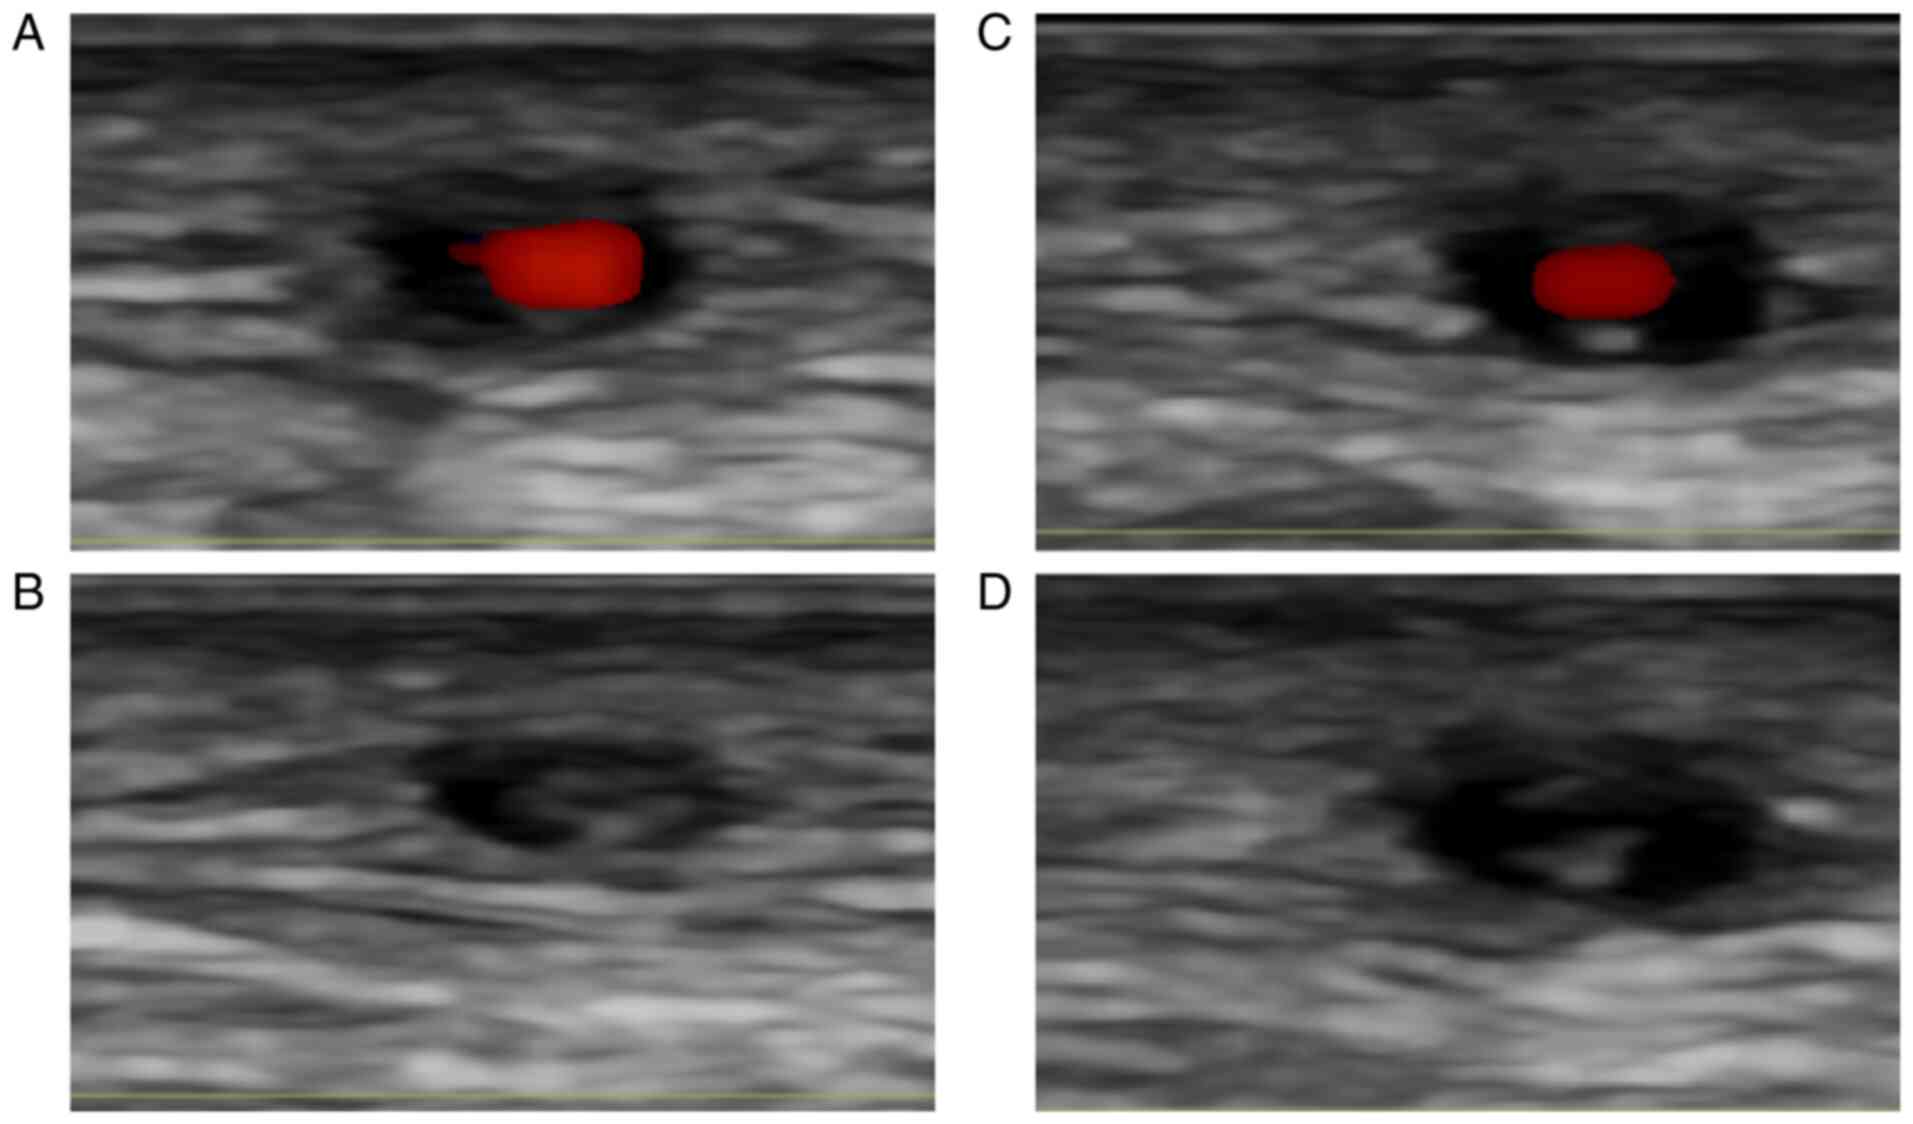

Stroke is a leading cause of death and disability worldwide. In addition to the classical etiologies of stroke as atherosclerosis and cardioembolism there are many unusual, rare causes, which require a high level of clinical suspicion and further investigations for correct and early diagnosis and adequate treatment. Giant‑cell arteritis or temporal arteritis, the most frequent vasculitis in the elderly population is one of the uncommon causes of stroke. In the setting of giant‑cell arteritis, stroke more likely affects the vertebrobasilar territory and is the main cause of mortality. Duplex ultrasound examination is a routine investigation for stroke patients and may be key to the diagnosis if the classical hypoechoic ‘halo sign’ is recognized at the level of vertebral arteries. In this situation the ultrasound evaluation of temporal arteries and temporal artery biopsy are mandatory. The Giant‑cell arteritis‑related stroke is a rare condition; therefore, there are no evidence‑based guidelines or standard recommendations for the treatment. In the present review, the main characteristics of giant‑cell arteritis-related stroke are discussed.

García-García J, Ayo-Martín Ó, Argandoña-Palacios L and Segura T: Vertebral artery halo sign in patients with stroke: A key clue for the prompt diagnosis of giant cell arteritis. Stroke. 42:3287–3290. 2011.PubMed/NCBI View Article : Google Scholar